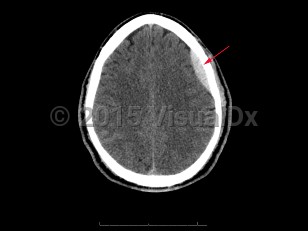

Epidural intracranial hematoma

The classic presentation involves a brief post-traumatic loss of consciousness, then several minutes to hours of a lucid interval, followed by obtundation and focal neurologic deficits. While this classic clinical description is widely taught, it is seen in < 20% of cases. Other less specific signs and symptoms include headache, nausea and emesis, seizures, neurologic deficits (contralateral weakness, hyperreflexia), papilledema, pupil-involving third-nerve palsy, somnolence, or coma.